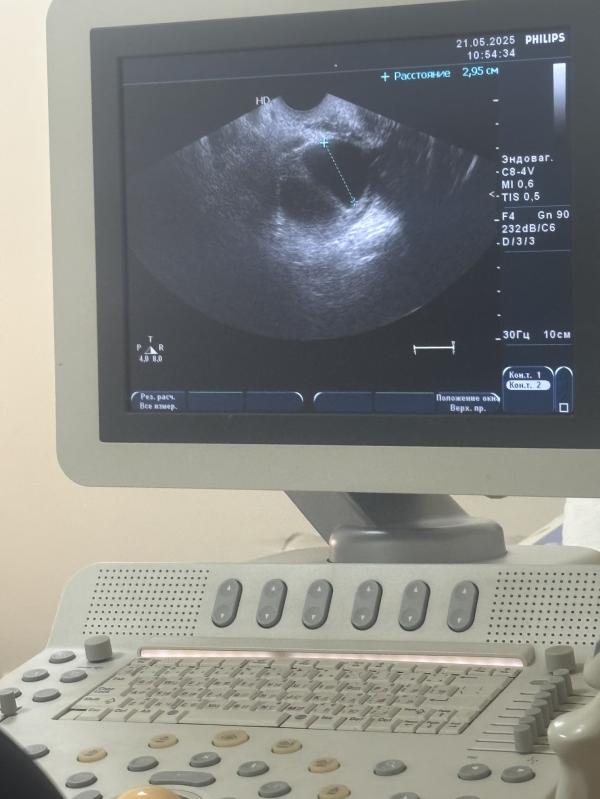

22 день цикла по узи яичник большого размера 55*44 с фолликулом 29 мм 🫣что дальше

@sonachka, киста огромного размера на яичнике завтра операция

@yulya.popova98.popova а почему операция, 29 мм огромная? Или неправильно изначально мерили?